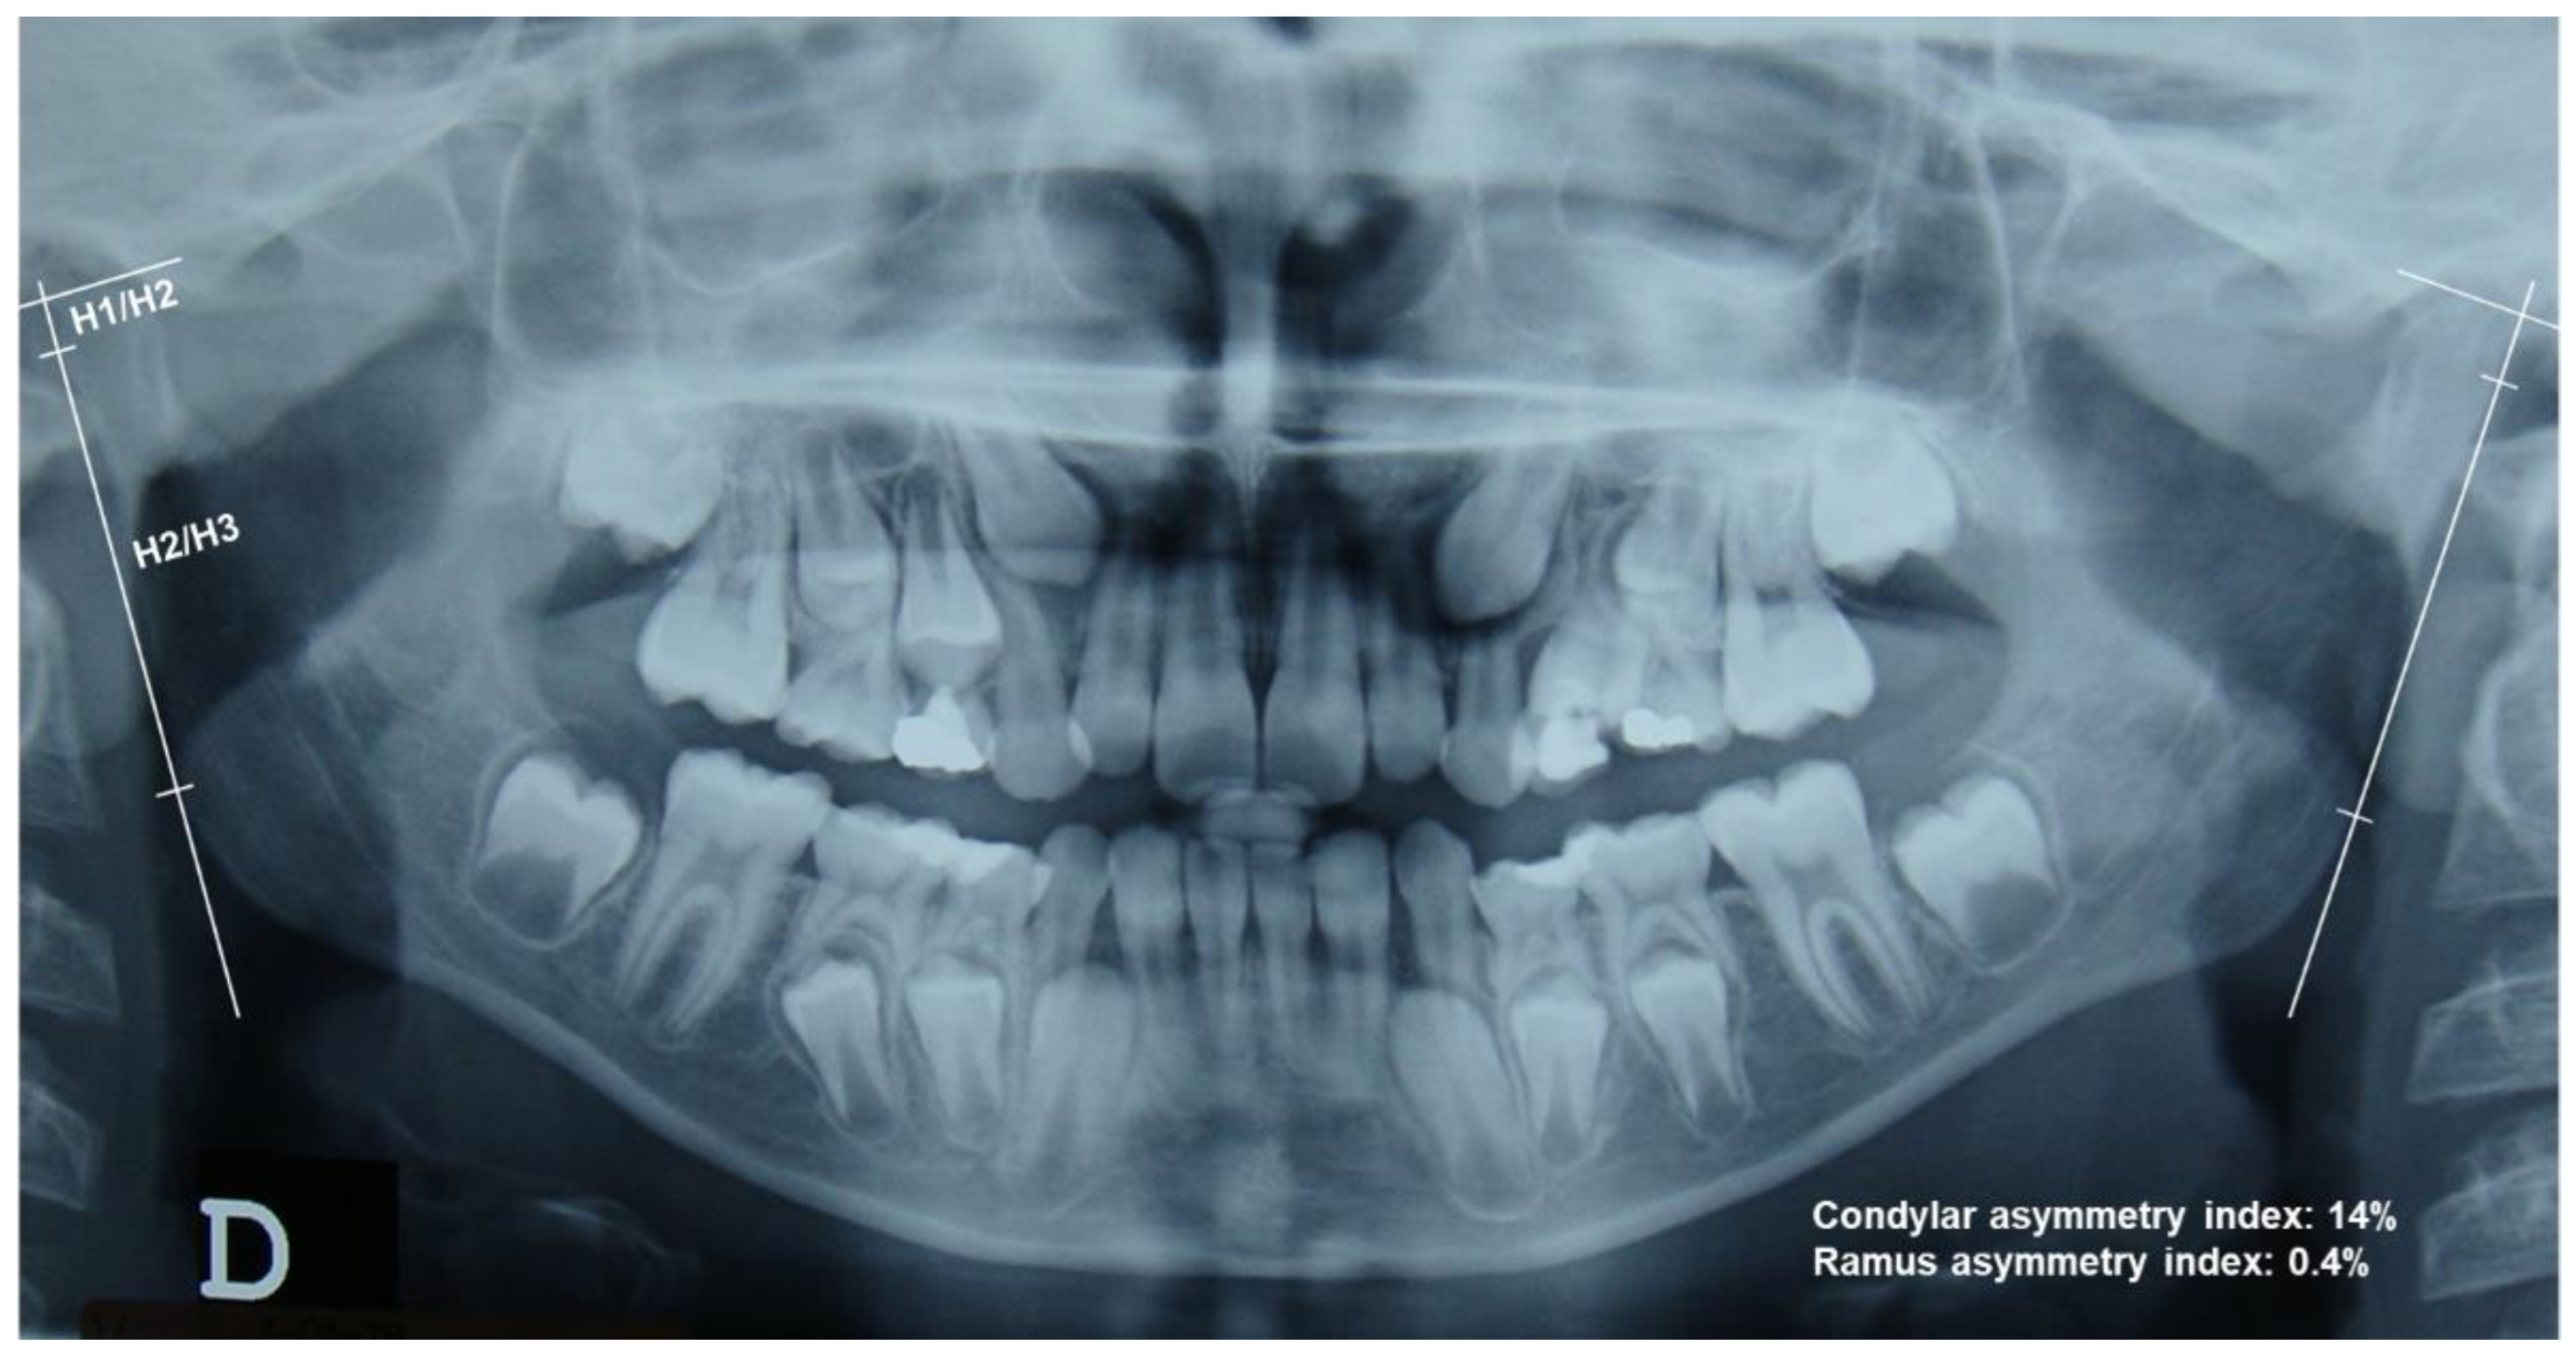

2.2. Measurements on OPGs

- Diéguez Pérez, M.; De Nova García, J.; Mourelle Martínez, M.R.; Feijoo García, G. Indicators of jawbone asymmetry through analysis of panoramic radiographs. Eur. J. Paediatr. Dent. 2016, 17, 136–140. [Google Scholar] [PubMed]

| † Asymmetric condyles [proportion] | 73% | 21% | p < 0.0001 |

| ‡ Mean asymmetry index—Condyle | 10.7% (9.0) | 4.2% (3.3) | p < 0.001 |